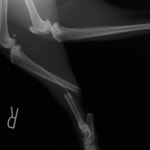

ペルシャ猫 11ヶ月齢 雄

他院にて左大腿骨遠位の成長板骨折(salter-harrisⅠ型)が認められており、治療相談を目的として来院。当院にて、キルシュナーワイヤーを用いたピンニングにより骨折部位の整復を行いました。術後の経過は良好で、現在も経過観察中です。

術後レントゲン

Arthrex社のターゲティングデバイスを用いてピンニングの位置を調整することで、確実な固定を行っています。当院ではこの手術器具以外にも、人の手術にも使用される様々な器具を導入し、手術精度を高め、また医療メーカーと新しい器具の開発、試作にも取り組んでおります。